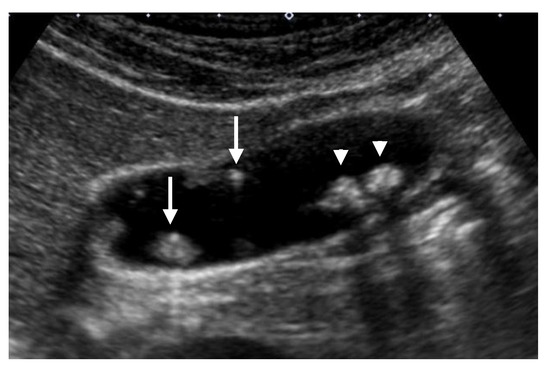

The progression of GBCs includes lateral spreading on the mucosal surface (horizontal progress) and deep invasion in the wall (vertical invasion). Lateral spreading is the main route in early-stage GBCs. According to a clinicopathological study on early GBCs, 10% of pedunculated and 75% of sessile GBCs were accompanied by laterally spreading components [10]. Eguchi et al. [45] reported that 66% of early GBCs had superficial spread of carcinoma, and sessile type or superficial raised type was more associated with superficial spreading than pedunculated type. Wakai et al. [46] also reported that 88% of sessile early-stage GBCs were accompanied by superficially elevated and/or flat tumors. US, especially with a high-frequency transducer with zoom magnification can detect localized slight thickening of the inner hypoechoic layer around GPLs (Figure 9), corresponding to the lateral spreading of flat-type GBCs [7,47].

Figure 9. Localized slight thickening of an inner hypoechoic layer around GPL. (a) HRUS delineated a localized slight thickening of an inner hypoechoic layer (arrow) around a sessile GBC (arrowhead). (b) Histopathologically, this finding corresponded to the laterally spreading of carcinoma (arrow). Reprinted with permission from ref. [7]. Copyright 2021 Japan Society of Ultrasonics in Medicine.